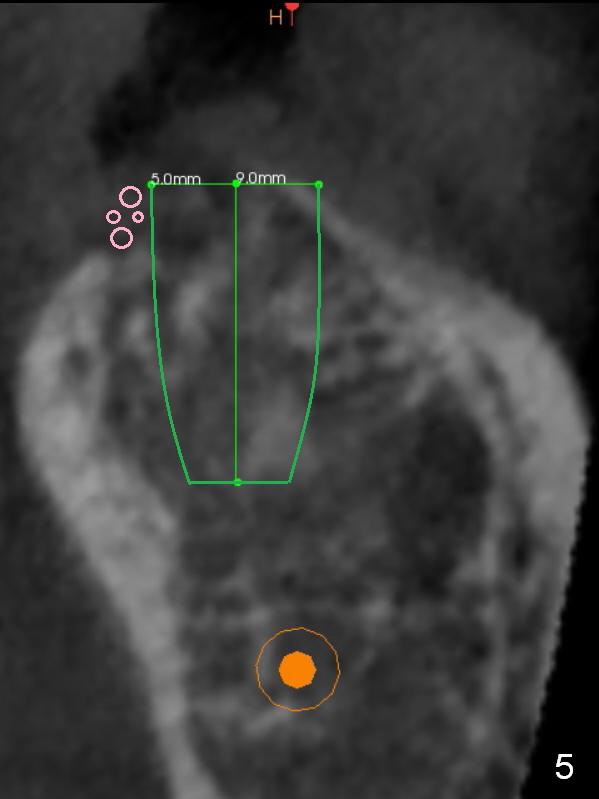

Preop palpation of the edentulous area at #18 does not show the flatness of the ridge top as shown by CBCT.  Incision reveals that the ridge is not as wide as CBCT indicates (Fig.1 (coronal section) between arrowheads).  In fact the ridge is concave (Fig.2 red dashed line).  Osteotomy is initiated in the middle of the concavity (Fig.2 green line) with insertion of 7 mm guide pin (Fig.3).   After removal of the pin, the osteotomy is moved buccally (Fig.4).  After Marking Bur and 4.3 mm Magic Drill, a 5x9 mm IBS implant is placed with 2.8 mm clearance from the Inferior Alveolar Canal (Fig.6).  Following deepening the osteotomy with Final Drill, the implant is placed deeper (Fig.7).  The osteotomy happens to be established in the mesial socket, since the distal socket has not completely healed (Fig.6 yellow dashed line).  Granulation tissue is removed.  Since the lingual crest is lower than the buccal one (Fig.1 B), there is lingual thread exposure after implant placement (Fig.5).  The exposed thread is covered by bone graft (autogenous bone, allograft and Osteogen, Fig.5 pink circles).  Some of the graft is apparently pushed into the distal socket (Fig.7 yellow dashed line) post GBR and suture.  As the implant is placed twice, insertion torque is <10 Ncm (although the implant is stable).  A 5x3 mm healing abutment is placed (Fig.7 H).